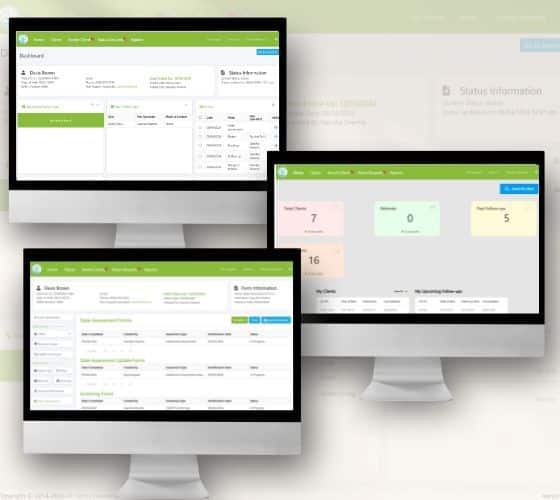

READ MORECase Study: Procentive – Empowering

Case Study: Procentive – Empowering Behavioral & Mental Health Management Through HIPAA-Compliant SaaS Problem Metric...

READ MORECase Study: Procentive – Empowering

Case Study: Procentive – Empowering Behavioral & Mental Health Management Through HIPAA-Compliant SaaS Problem Metric...